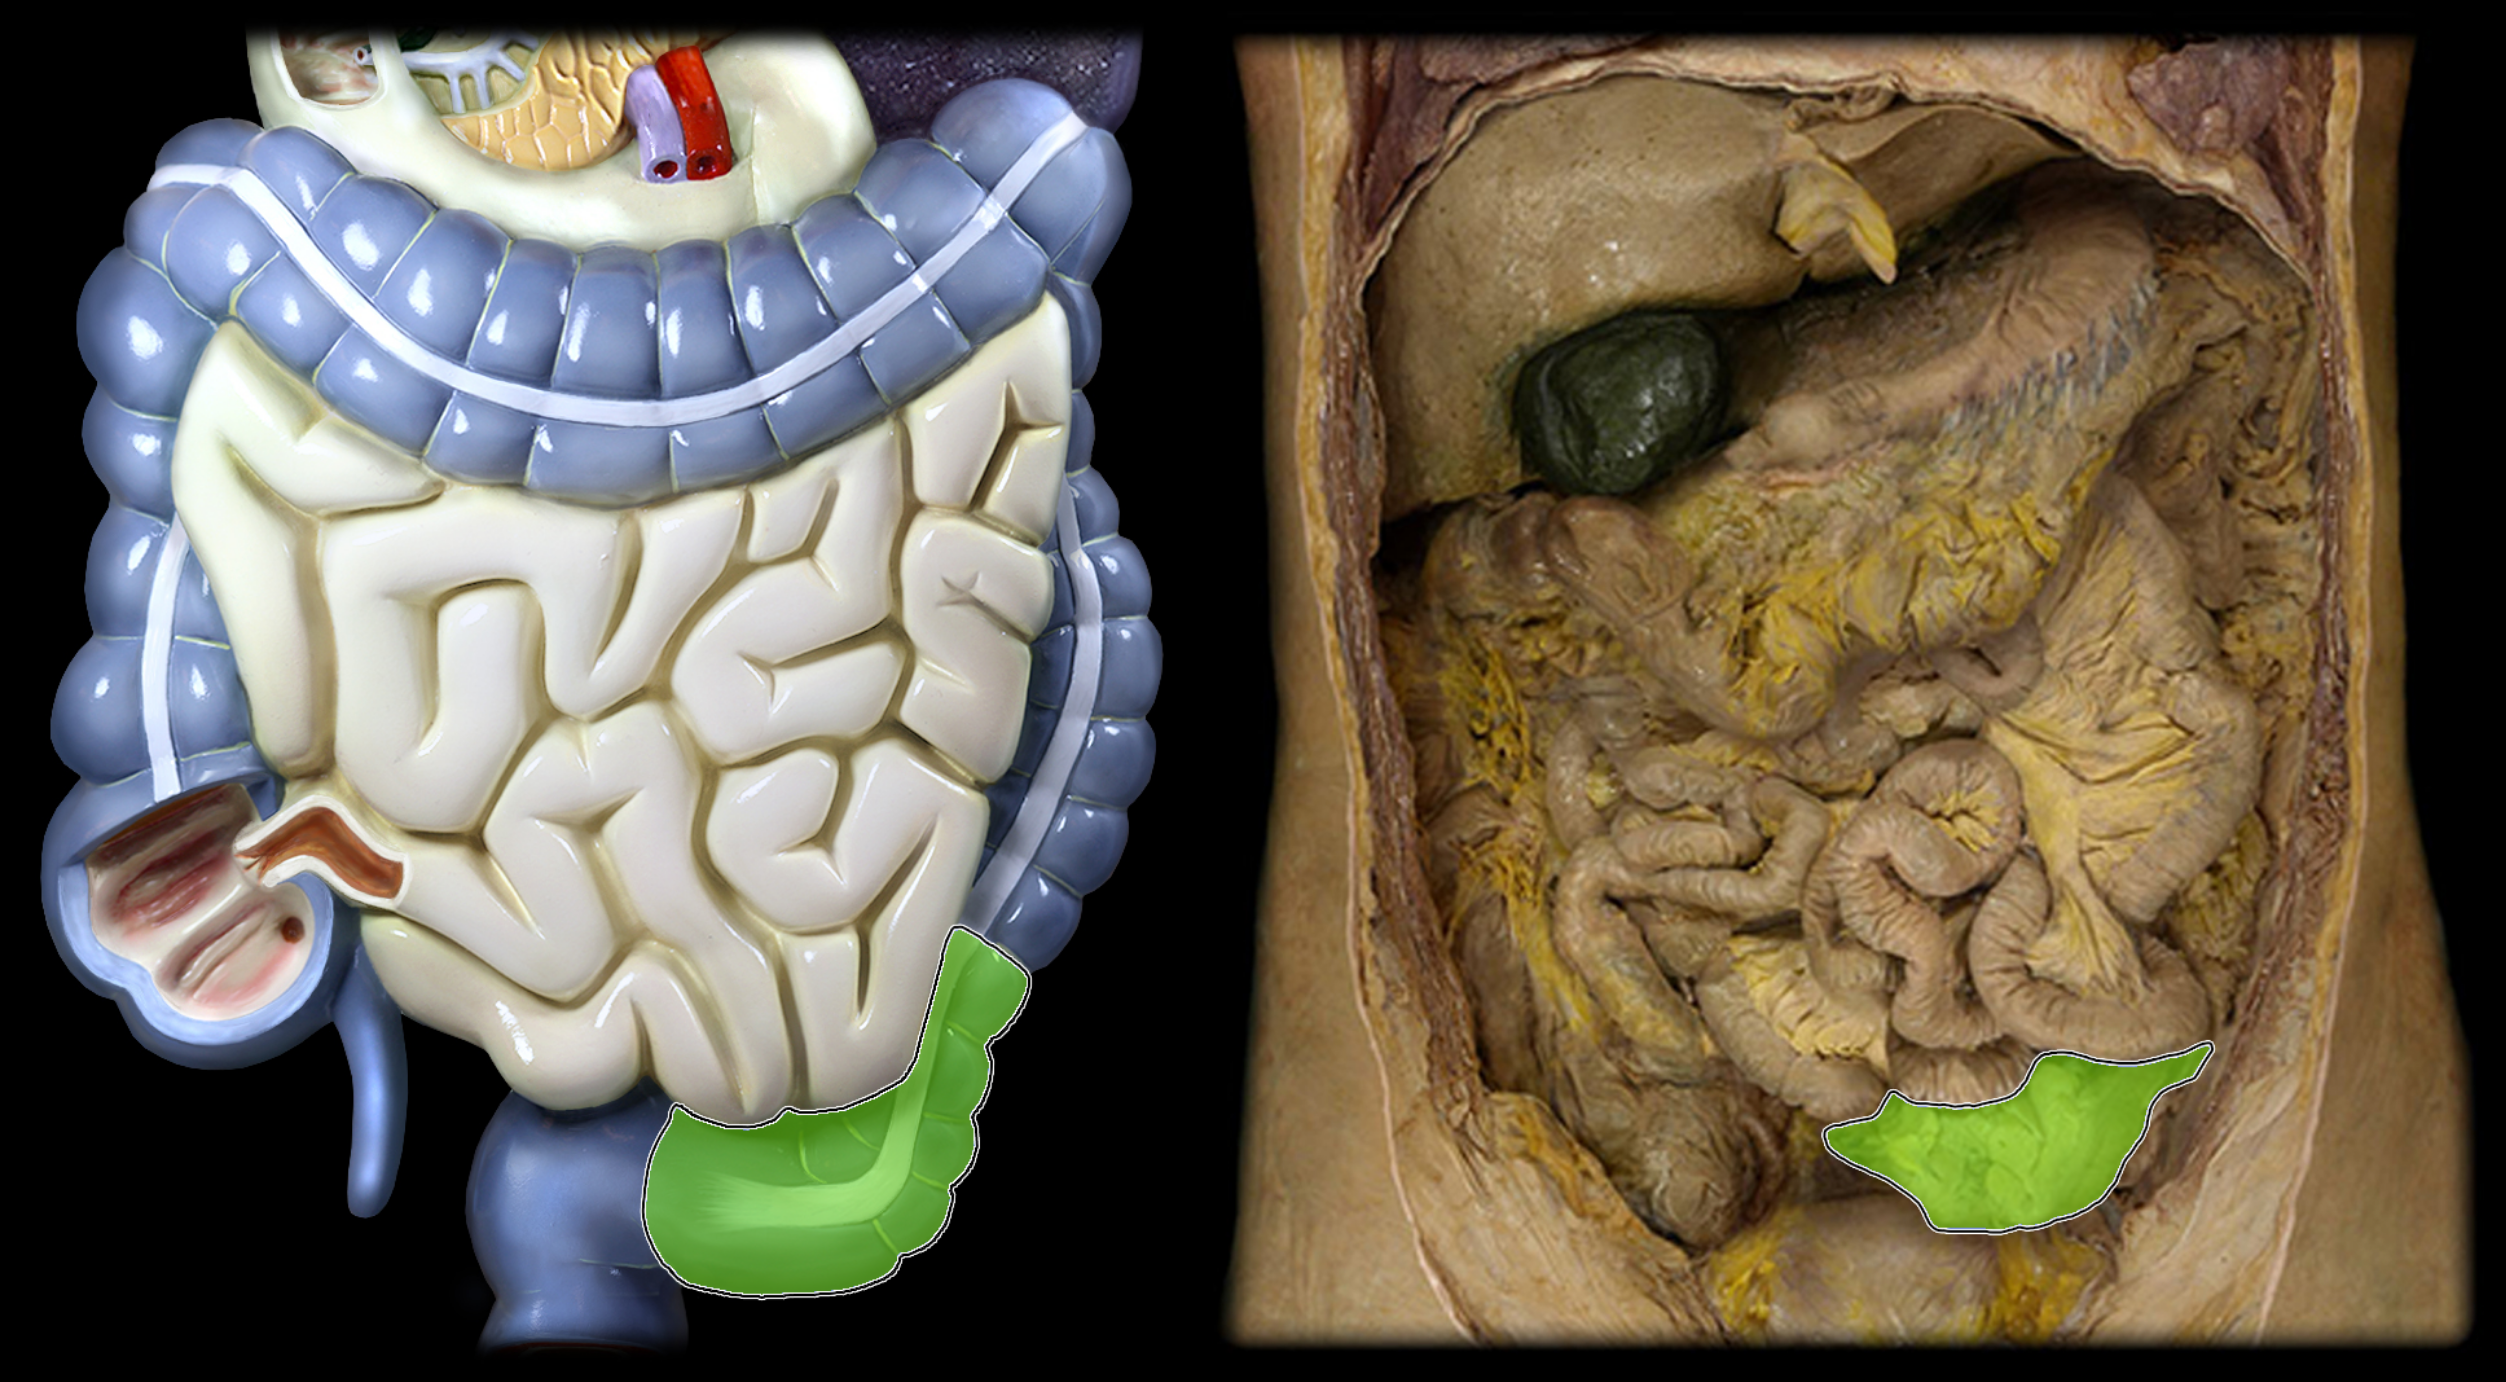

Cecum

Sigmoid colon

Jejunum

Ileum